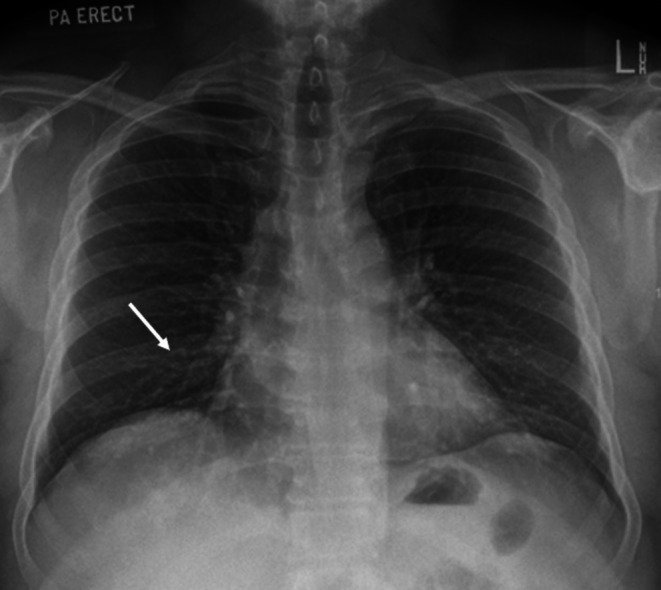

A middle-aged male presented with chronic cough, shortness of breath and fever. In the presence of wheeze and mild right-sided opacities on chest x-ray, he was treated for infective exacerbation of asthma with nebulised bronchodilators, antibiotics and steroids. Due to persistent wheeze, a contrasted computed tomography (CT) scan was done and revealed the presence of two endobronchial linear foreign body (FB) opacities, the second located more distally than the first. A rigid bronchoscopy-based technique under general anaesthesia was used to remove the first FB, and flexible bronchoscopy via endotracheal tube was used for the second FB in the same session. This case illustrates the tenets of airway FB diagnosis and management. The differential diagnosis of radiolucent airway FB needs to be considered in patients with chronic symptoms. Rigid and flexible bronchoscopy techniques are complementary. Peripheral lesions are more accessible by flexible bronchoscopy. Measures to ensure complete removal of FBs must be consistently incorporated into routine practice.